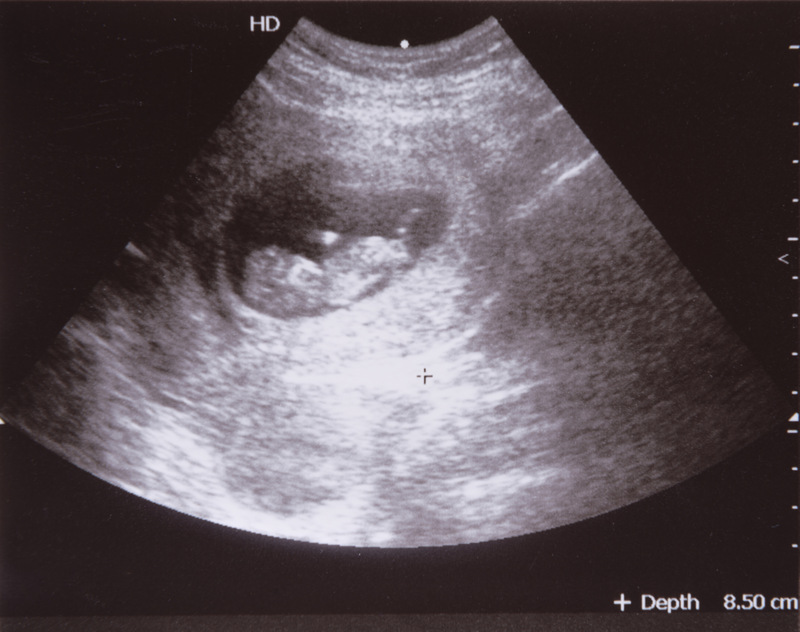

早期流产的主要原因中,胚胎和胎儿染色体异常是主要原因,约占50~60%,对于这部分流产,我们都知道,遵循自然界优胜劣汰的结果,我们补充再多的黄体酮也无益,所以对于初次妊娠先兆流产者,多考虑自然淘汰所致,无需进行过于积极的治疗。目前的保胎指证还是依据先兆流产的变现,如有停经史、阴道出血、有或无腹痛、子宫大小和停经孕周相符、超声提示宫内孕的情况下,对孕酮水平低者可以进行孕激素(黄体酮)治疗。